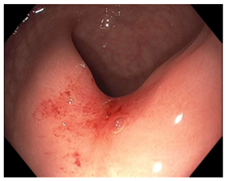

| Endoscopy | Flat white scar Telangiectasia Absence of ulcers and mucosal nodularity | Small mucosal nodules/minor mucosal irregularities Superficial ulceration Mild, persistent erythema of the scar | Visible tumor |

| Endoscopic Finding | |||

| Flat, white scar | ![]() | ![]() | ![]() |

| Telangiectasia | ![]() | ![]() | ![]() |

| Small mucosal nodules, minor mucosal irregularities | ![]() | ![]() | ![]() |

| Superficial ulceration | ![]() | ![]() | ![]() |

| Persisting erythema of scar | ![]() | ![]() | ![]() |

| Complete Response | Near-Complete Response | Incomplete Response |